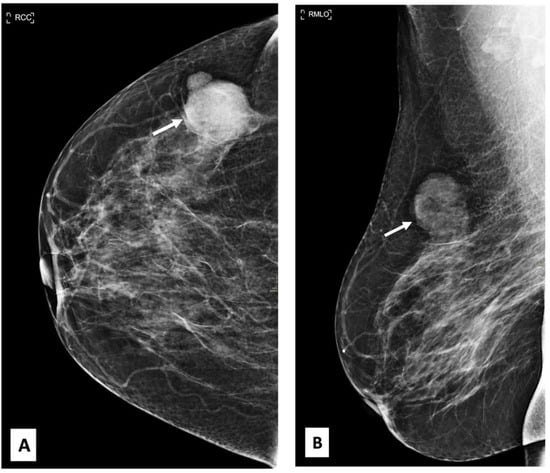

A 54-year-old woman came to our facility for the screening procedure. A mammogram was performed on her. The patient had no remarkable medical or family history, and she was here for routine screening. Mammography showed focal asymmetry of equal density in the upper-outer quadrant of the right breast, which was 9 cm distant from the nipple. The focal asymmetry was 1 cm in size. This finding partially persisted in the additional targeted compression view (Figure 1). The targeted ultrasound examination did not reveal any findings that were suitable for inclusion in the criteria. After an additional nine months had elapsed, a breast mass in the axillary region of the right breast was identified as being the source of her symptoms. During the clinical examination, it was discovered that the patient had a mass that was uncomfortable, moveable, and irregularly shaped and that measured 2 × 2 cm2.

Figure 1. Craniocaudal (CC), mediolateral oblique (MLO), and MLO compression view mammography. (AC) show a partial persistent oval-shaped fat containing 1 cm of focal asymmetry in the upper-outer quadrant of the right breast (arrows).